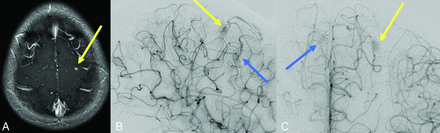

The findings of Engel et al discussed above can also be interpreted to support screening for brain VMs in children with HHT. Even if all 13 children with high-flow brain VMs and HHT had been diagnosed with HHT before brain VM clinical presentation, almost one-half would have presented with hemorrhagic stroke in the absence of screening,25 a number that the authors deem unacceptably high. Figure 2 shows images from a child with HHT who presented with a life-threatening cerebellar hemorrhage due to a brain AVM. The AVM could have been successfully treated before the hemorrhage occurred if it had been detected on screening. Figure 3 shows images from a 2-month-old infant whose pial AVF was identified on screening and who underwent successful embolization at 6 months of age when surveillance imaging demonstrated progression. The embolization was without complications and resulted in obliteration of the AVF. Findings of repeat imaging performed 7.5 years after treatment were stable without AVF recurrence. The child is neurologically and cognitively healthy at 9 years of age. Figure 4 shows MR imaging and subsequent DSA from a girl with ENG-related HHT. The DSA demonstrated the subtle finding on MR imaging in greater detail and identified a second small AVM that was not visible on MR imaging.

A girl diagnosed with HHT due to a familial ENG variant had screening MR imaging that revealed a punctate area of enhancement in the left posterior frontal lobe surrounded by a subtle halo of enhancement (yellow arrow) on a high-resolution 3D T1 postgadolinium image (A). This finding corresponds to a subcentimeter AVM nidus (yellow arrow) on lateral (B) and anterior-posterior (C) DSA. An additional subcentimeter AVM nidus (blue arrow) supplied by the contralateral anterior cerebral artery is also identified on DSA.